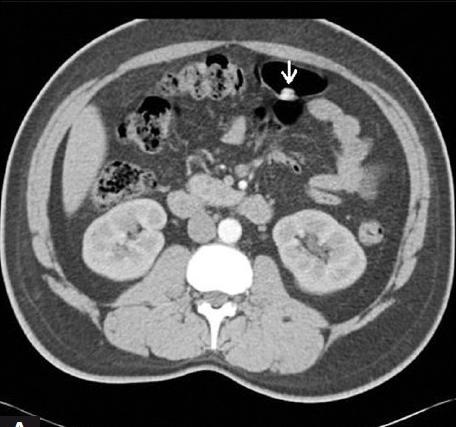

Image radiologique TDM

des

polyps du colon est aspect laculaire a sessile ou polypoide

a hyper-dense avec pedicule intra luminal du colon . Sa

nombreuse peut de quelque d'un au colon a multiple

polype s'etendre le long du colon .

Aspect du polyp

laculaire hyperdense a bord lisse et a sessile

rehaussement intraluminale du colon ( fleche blanche

) . Image TDM du polyp du colon ean coupe axiale . |